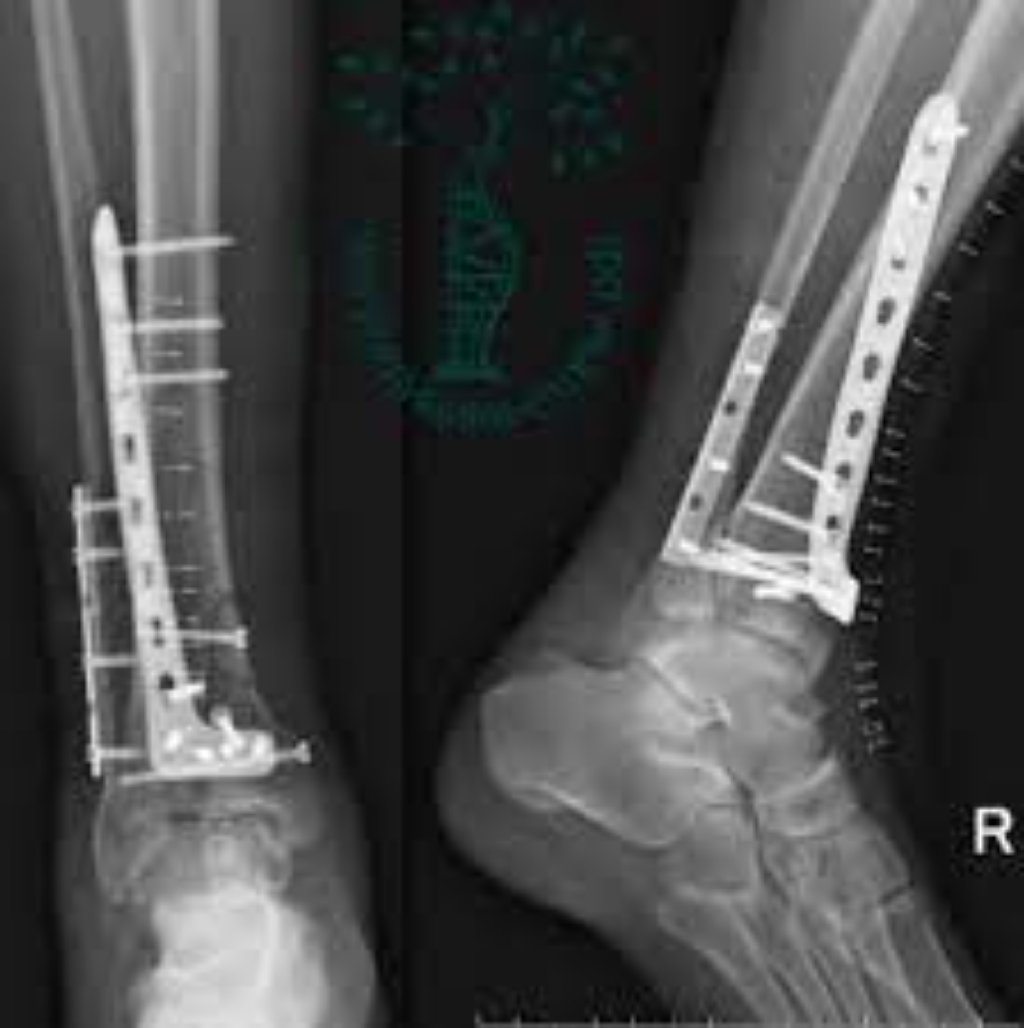

Plitə və Vida Osteosintezi: Bu, ən çox yayılmış osteosintez üsullarından biridir. Sınıq sümük parçal ...